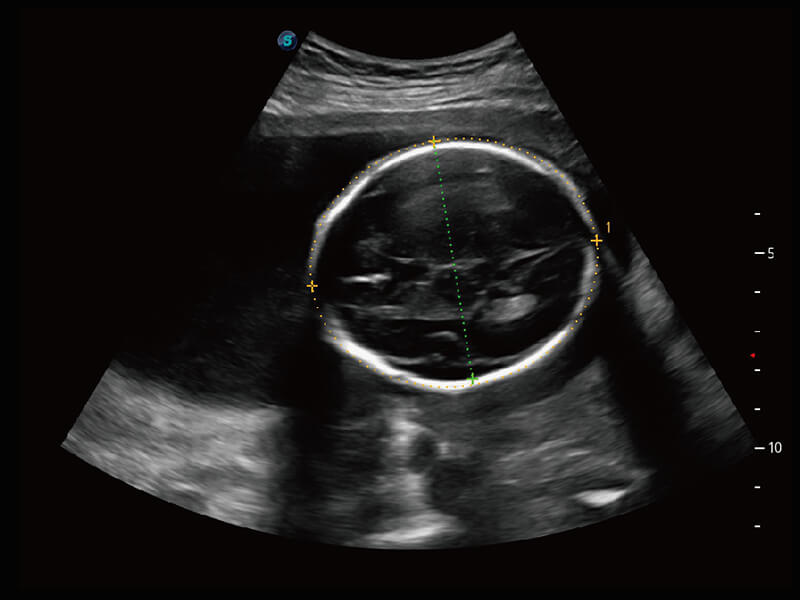

S60探头工艺,从前端信号处理每一个环节采集无损声学数据,真实还原组织原貌,再现解剖细节。

• 腹部单晶体探头( C1-6A )

高分辨率容积成像 栩栩如生

超宽频带技术,为容积成像带来优质的二维图像基础,为您呈现丰富的结构细节,栩栩如生地展示宝宝的宫内形态以及各种组织的立体结构。